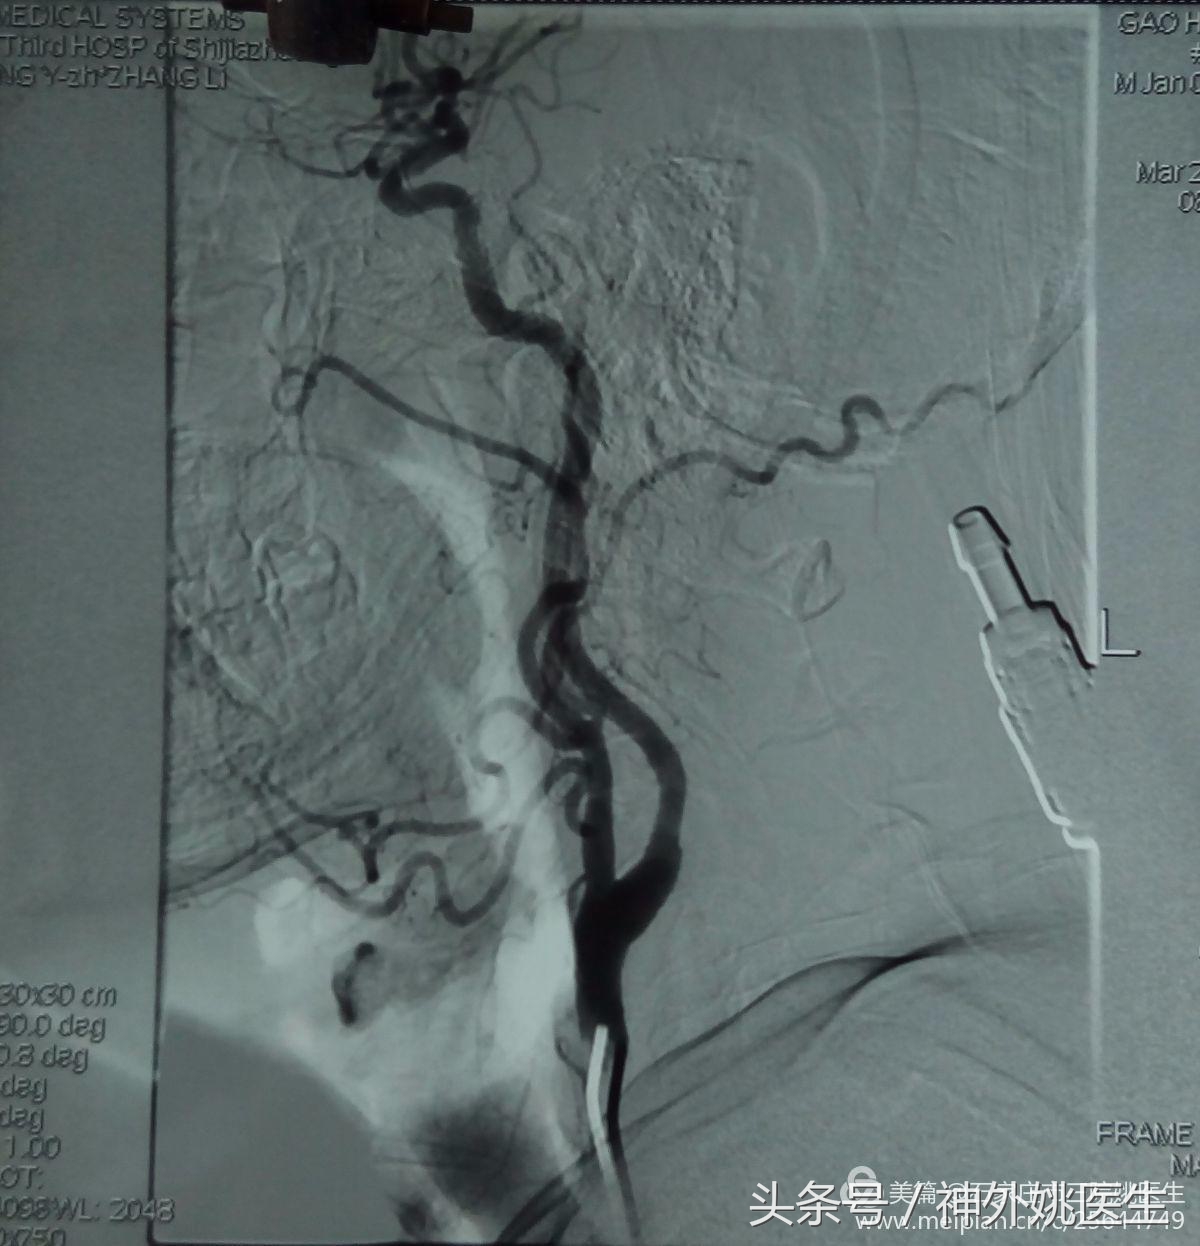

3.左颈动脉造影示:左颈内动脉起始部轻度狭窄(图10)。

图10

4.左颈内动脉颅内段造影示:左侧大脑前动脉A1段供应双侧A2,前交通动脉开放(图11)。

(图11)